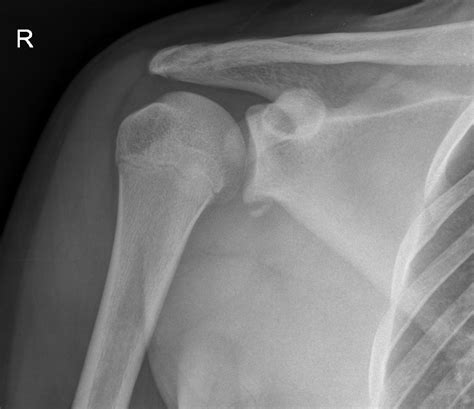

Top doctors who treat osteoarthritis.